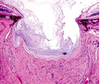

What ocular abnormality is present?

Corneal edema

Causes of corneal opacity

Corneal edema- MOST COMMON- fluid in the corneal stroma

– Injury to epithelium (ulceration)

– Injury to endothelium

• Cornealendothelial

dystrophy

• Increased IOP (Glaucoma) • Immune-mediated

– Keratitis–neovascularization has leaky capillaries

Corneal deposits – covered later

Corneal edema due to an ulcer

Ulcer stains green with flourescein dye

Corneal edema due to keratitis

Note gross features of inflammation

MDx: diffuse corneal edema